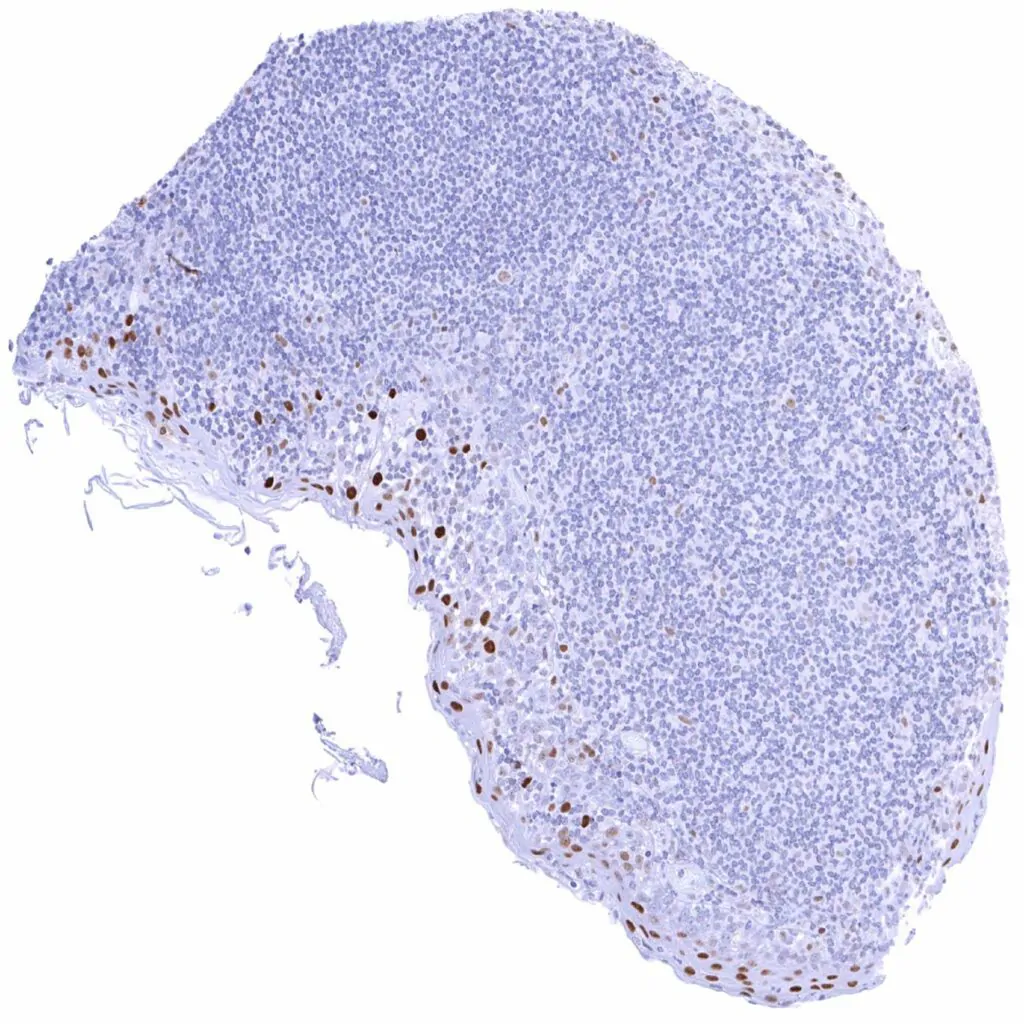

Thymus – Strong Cyclin E1 staining of some regularly distributed cells (thymic epithelial cells_). Weak Cyclin E1 staining of some lymphocytic cells